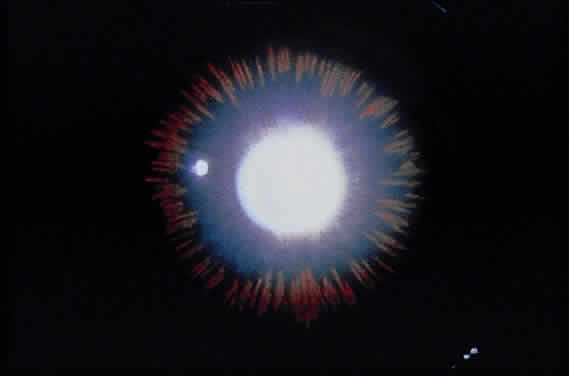

Iris changes include deposition of pigment on the anterior iris surface and midperipheral iris transillumination defects of the iris pigment epithelium.166 If pigment deposition on the anterior iris surface is asymmetrical, heterochromia may be noted.166,182 In some asymmetrical cases, greater pigment dispersion has been noted in eyes with angle recession183 and in the cataractous eye in patients with unilateral lens opacities.184 The transillumination defects, which vary in severity from a few spokelike changes to 360° of involvement, can be seen by retroillumination achieved by directing a light through the pupil or by scleral transillumination166,185,186 (Fig. 15). A technique known as infrared transillumination videography allows visualization and documentation of iris defects that may not be visible on slit-lamp examination.187

Fig. 15. Spokelike midperipheral iris transillumination defects in pigmentary glaucoma as seen by retroillumination.